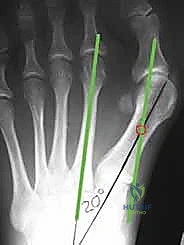

الصورة توضح مفهوم "التصحيح المثالي" لورم إبهام القدم، حيث يتم رسم خط موازٍ للعظم المشطي الثاني يلامس قاعدة العظم المشطي الأول. يساعد هذا التخطيط الدقيق الأستاذ الدكتور محمد هطيف في تحديد مكان ودرجة التحريك اللازمة للعظم المشطي بدقة متناهية.

تعتبر الأشعة السينية أثناء الوقوف (تحمل الوزن) أداة التشخيص الأساسية. يقوم الأستاذ الدكتور محمد هطيف بقياس زاوية (HVA) وزاوية (IMA) بدقة لتحديد الخطة الجراحية المناسبة.

الدقة هي مفتاح النجاح. يوضح هذا التخطيط كيف يقوم الدكتور هطيف بحساب زوايا القص العظمي بالملليمتر قبل بدء الجراحة لضمان استعادة الميكانيكا الحيوية السليمة للقدم.